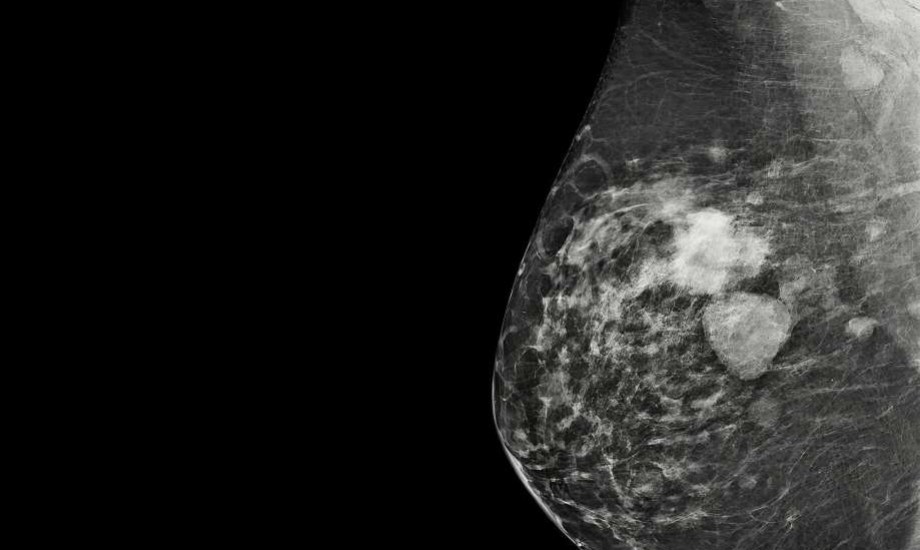

سرطان الثدي متعدد البؤر يسبب ظهور أكثر من ورم في الثديسرطان الثدي متعدد البؤر يسبب ظهور أكثر من ورم في الثدي

سرطان الثدي متعدد البؤر هو أحد أنواع السرطان، الذي يسبب ظهور أكثر من ورم في الثدي، وتنشأ هذه الأورام من الورم الرئيسي، وتكون موجودة في نفس المنطقة من نفس الثدي، نقلاً عن "Verywellhealth".

وتشير التقديرات إلى أن سرطانات الثدي متعددة البؤر تمثل حوالي 10% إلى 60% من جميع حالات سرطان الثدي، كما أظهرت الأبحاث أن المصابات بـ سرطان الثدي متعدد البؤر أكثر عرضة لخطر الإصابة بالورم الخبيث من أولئك الذين يعانون من سرطان الثدي أحادي البؤر، وهذا يعني أن الخلايا السرطانية يمكن أن تنتشر خارج أنسجة الثدي إلى العقد الليمفاوية ومناطق أخرى من الجسم.

يمكن اكتشاف السرطان بالأشعة السينيةيمكن اكتشاف السرطان بالأشعة السينية

2-تصوير الثدي بالأشعة السينية: تصوير بالأشعة السينية للثدي يتم إجراؤها إما للفحص أو التشخيص.